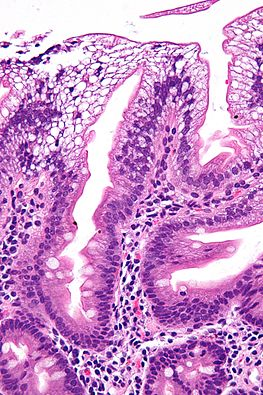

Staining Techniques

To overcome the lack of natural pigments, specimens are often prepared with a stain. There are many different stains which are used to distinguish different parts of a cell. Staining is commonly used in tissue samples.